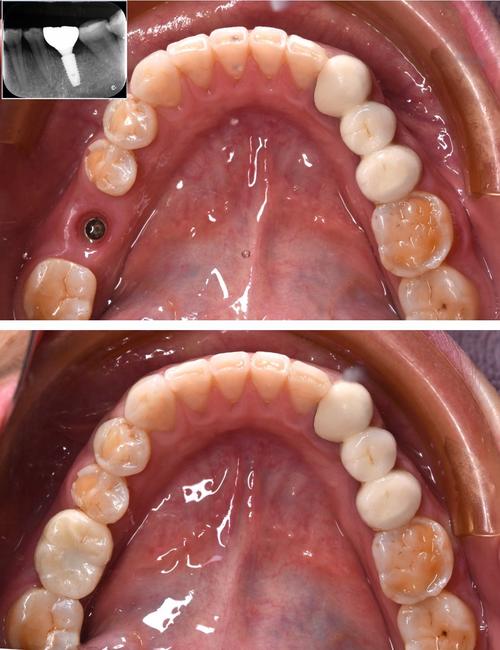

种植体失败后需二次种植者

部分患者因初次种植失败(如种植体松动、脱落、周围炎等)后,取出种植体,此时拔牙窝内的牙槽骨可能因炎症刺激或机械损伤而进一步吸收,导致骨量不足,种植体周围炎会导致牙槽骨“溶解”,形成骨缺损,若直接二次种植,可能因骨量不足导致种植体稳定性差。

这类患者需先控制炎症(如牙周基础治疗、抗生素应用),待炎症消退后,通过植骨手术恢复拔牙窝的骨量,常用的植骨材料包括自体骨(如拔牙窝内的碎骨)、人工骨(如羟基磷灰石、β-磷酸三钙)等,植骨后需等待3-6个月,待骨结合完成后再进行二次种植。